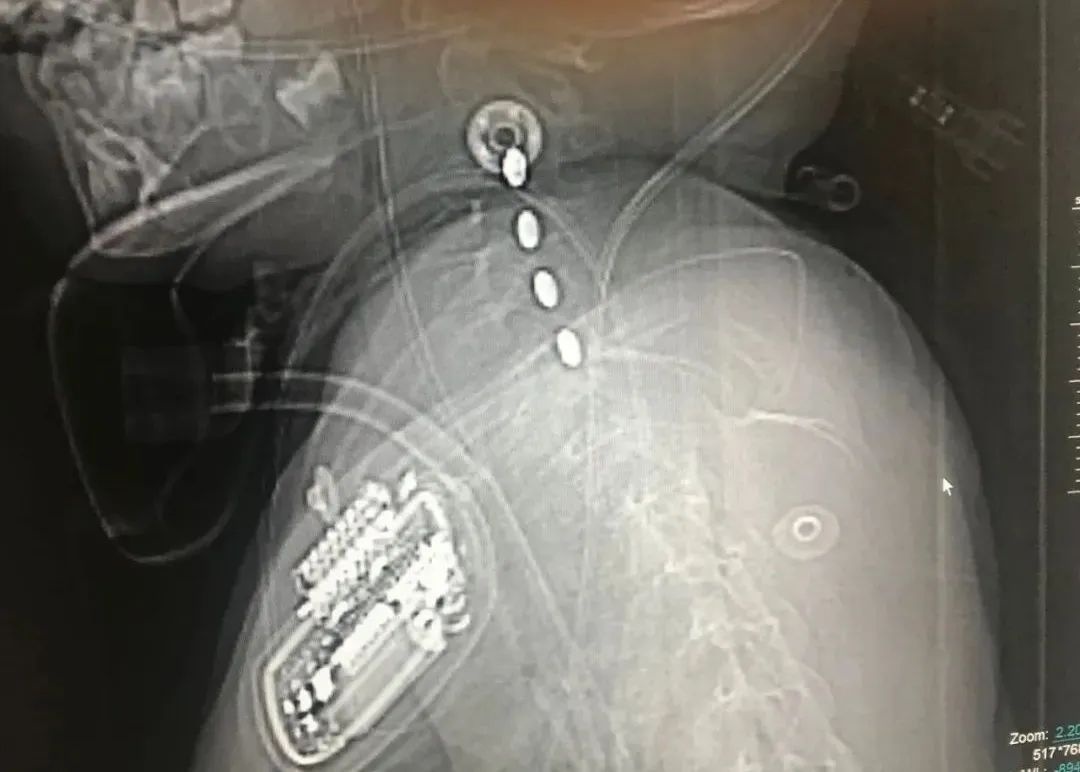

11.04,因患者左肩关节疼痛伴活动障碍,行“左锁骨骨折切复内固定术”。

手术前

手术后